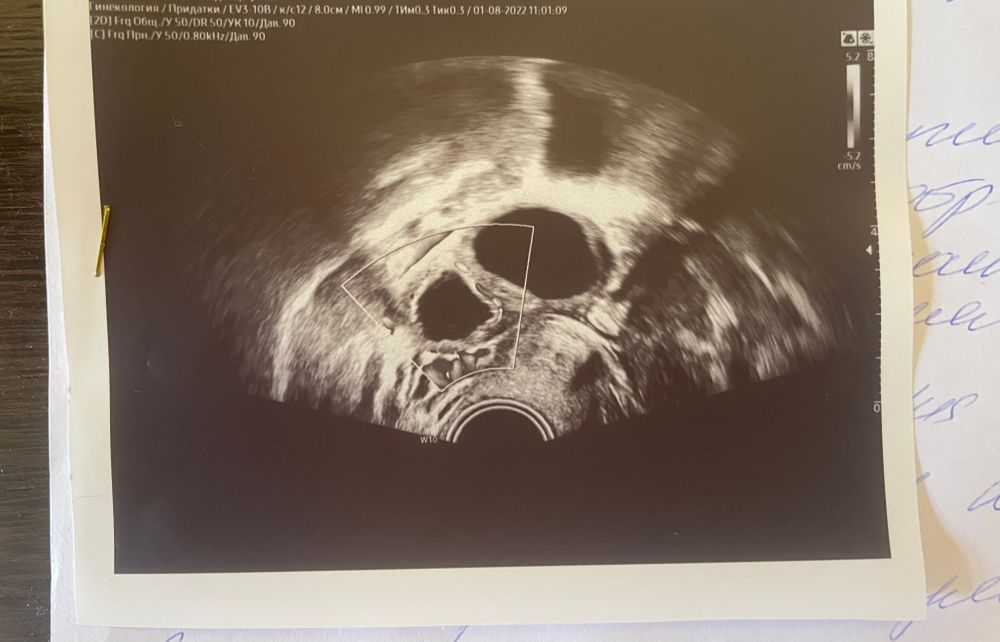

Желтое тело есть или нет?

Два доминантных фолликула, был укол хгч, была на узи и узист поставила под вопросом ЖТ то что меньше